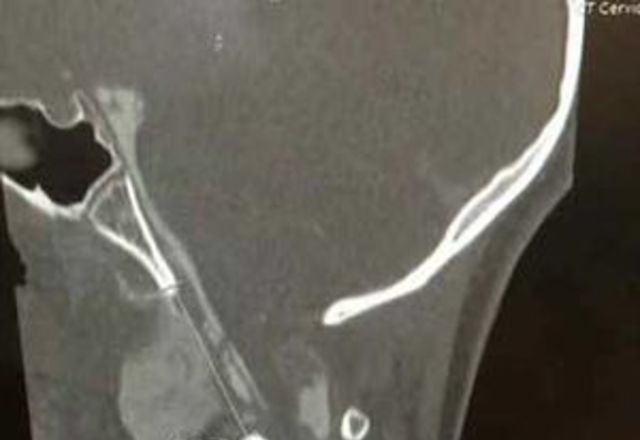

Atlanto-occipital dislocation

A disruption of the connection (ligaments) between the skull and the first cervical vertebra (C1).